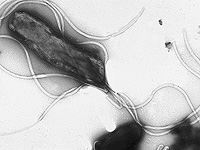

Ранее считалось, что язвы желудка возникают из-за острой пищи или неправильного питания. Однако современные исследования показали, что основной причиной большинства язв и повышенного риска рака желудка является бактерия Helicobacter pylori, которой заражены более 60% населения мира. Сегодня ученые биологического факультета Школы естественных наук и инженерии Университета Атенео де Манила разрабатывают вакцину против этой бактерии, которая потенциально может предотвратить язву желудка и снизить риск рака этого органа.

Ученые из Ateneo выявили ключевые белки H. pylori, которые позволяют бактерии выживать в кислой среде желудка, закрепляться на слизистой и уклоняться от действия иммунной системы. Они также определили фрагменты этих белков, которые, по прогнозам, безопасны, не вызывают аллергии и способны активировать защитные иммунные клетки.